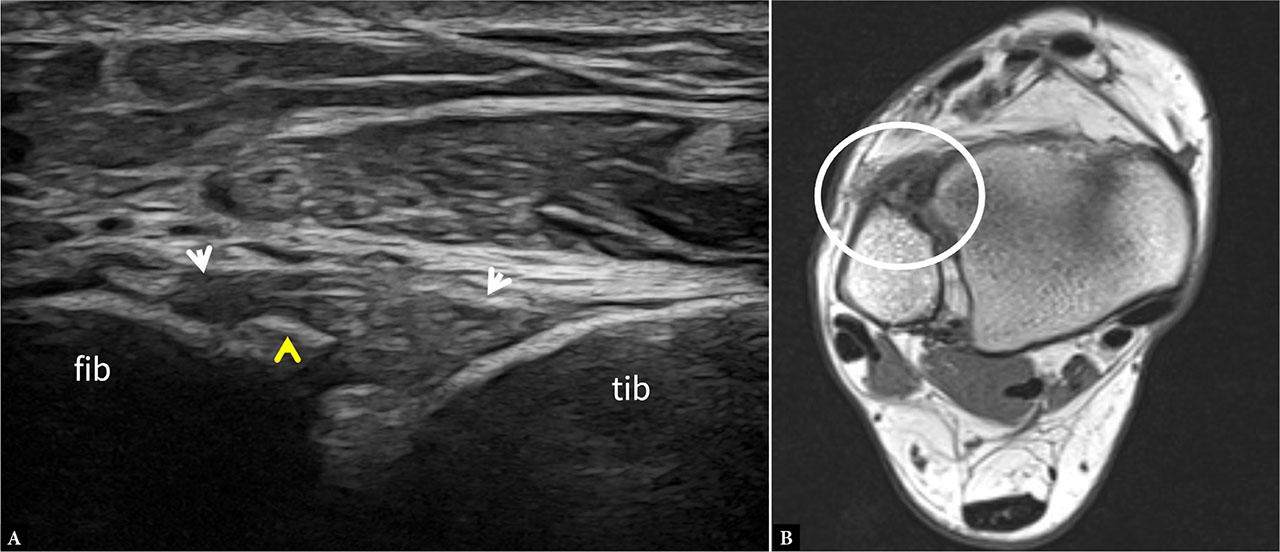

Chronic AiTFL tear. A. US image demonstrates an irregular and heterogeneous AiTFL with hypoechoic fibrotic changes at the fibular insertion (white arrows). In addition, there is a small, avulsed bone fragment seen at the fibular attachment (yellow arrowhead). Axial T1W image (B) of the same patient confirms a thickened, heterogeneous AiTFL (white circle). Note that the small bone fragment is not well-visualized in the MRI image